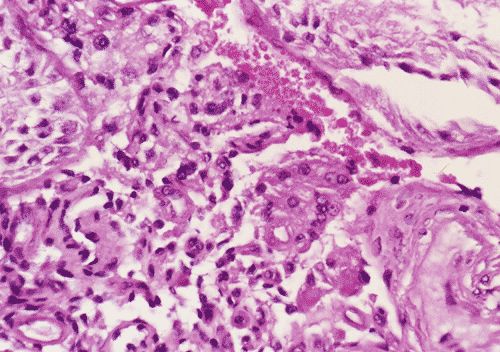

On low-magnification (Panel A), the diameter of the seminiferous tubules appeared to be slightly decreased. There is, however, no thickening of the basement membranes, interstitial fibrosis, or inflammation. On medium and high- magnification (Panel B and C),the seminiferous tubules are lined by columnar Sertoli cells which have triangular to ovoid nuclei, pale-staining chromatin, and prominent central nucleoli. The salient feature is the total lack of spermatogenesis (Panel C). The interstitium contains a few scattered clusters of Leydig cells without definitive evidence of hyperplasia (Panel D).

DIAGNOSIS: Sertoli cell-only syndrome (germinal cell aplasia), mature (adult) variant.

In the mature variant, the seminiferous tubules are lined by mature-appearing columnar Sertoli cells, some which have roughly triangular (so-called tripartite) nuclei and/or vacuolated cytoplasm. Seminiferous tubular diameters are smaller than in normal adult testes, but larger than in immature SCOS; tubular lumens are open. The putative pathogenesis is failure of migration of germ cells from the primitive yolk sac to the gonadal ridge. In spite of this, the Sertoli cells, under normal hormonal regulation, develop relatively normally. Some patients with mature SCOS have a history of viral orchitis; many cases are idiopathic.